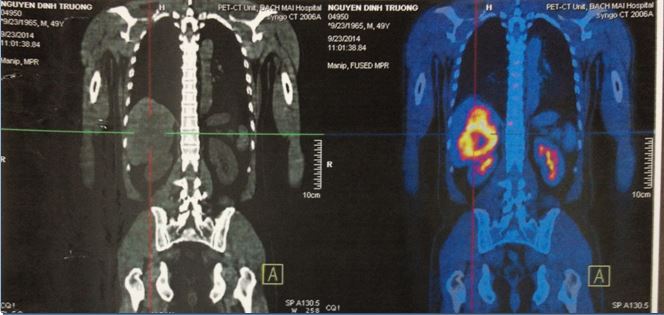

PET/CT

Hình 2: Hình ảnh khối u hạ phân thùy VI 8,6x7,0 cm, max SUV=7,49; khối u gan trái 3,0x2,0 cm, maxSUV=5,06